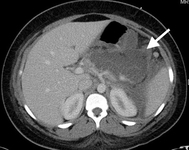

Tomografia computadorizada (TC) de adolescente do sexo feminino que apresenta dor abdominal na região médio-epigástrica resultante de pancreatite biliar. A grande coleção de fluidos no leito pancreático (seta branca) e a ausência de realce pancreático sugerem necrose liquefativa do pâncreas